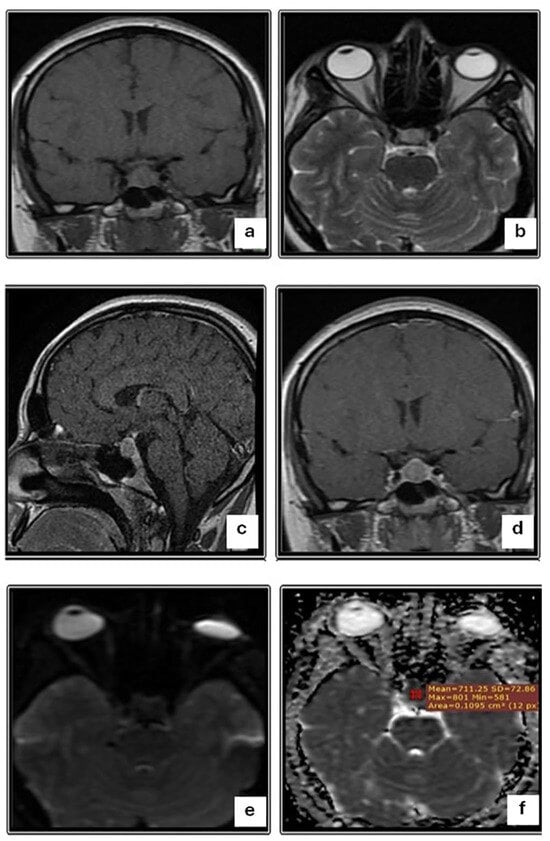

| T2W1 | 0.001 | |

| Iso-intense | 0 (0) | |

| Hypo-intense | 12 (28.6) | |

| Hyper-intense | 33 (73.3) |

| DWI (b 100) | <0.001 | |||

| Iso-intense | 9 (20.0) | 9 (33.3) | 0 (0) | |

| Hypo-intense | 15 (33.3) | 0 (0) | 15 (83.3) | |

| Hyper-intense | 21 (46.7) | 18 (66.7) | 3 (16.7) | |

| ADC map | 0.004 | |||

| Hypo-intense | 21 (46.7) | 18 (66.7) | 3 (16.7) | |

| Hyper-intense | 15 (33.3) | 0 (0) | 15 (83.3) | |

| ADC value, Mean ±SD (range) | 0.72 ± 0.25 (0.40–1.10) | 0.54 ± 0.19 (0.42–0.90) | 0.95 ± 0.08 (0.90–1.10) | 0.008 |